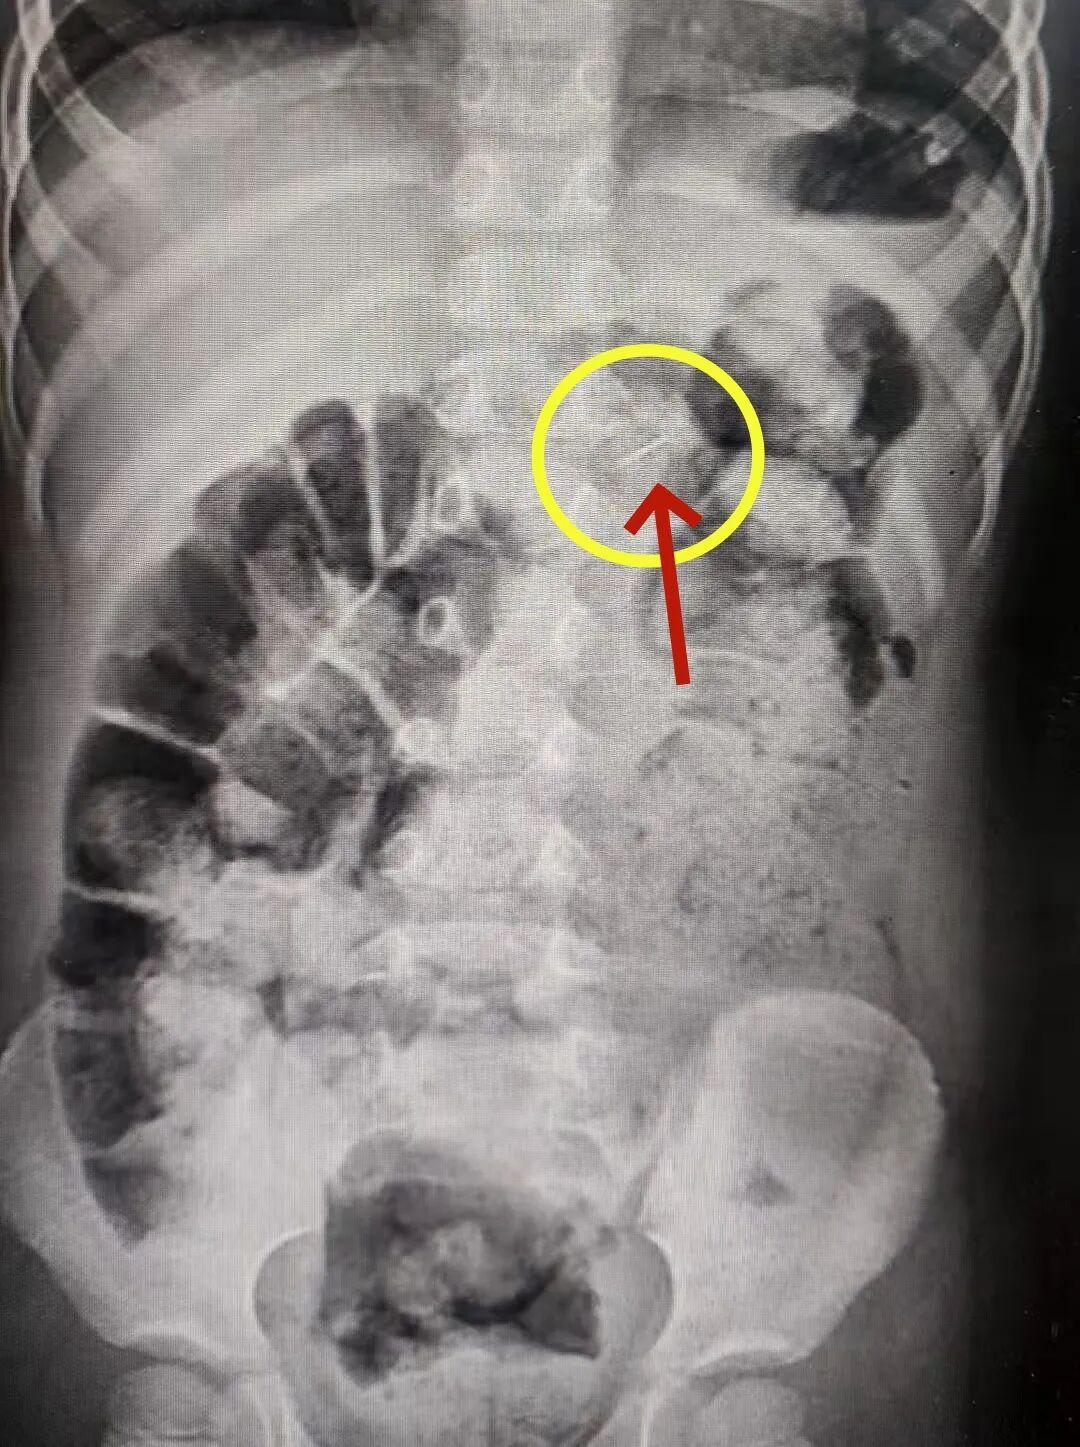

接诊医生高度警惕,第一时间安排影像学检查。片子清晰显示胃内一枚针状异物。

急诊科医生紧急联系消化内科医生进行进一步的判断:胃肠黏膜很薄,肠壁也很薄,尖锐断针可能会随着胃蠕动进入肠内导致穿孔。情况危急,必须连夜手术取出!